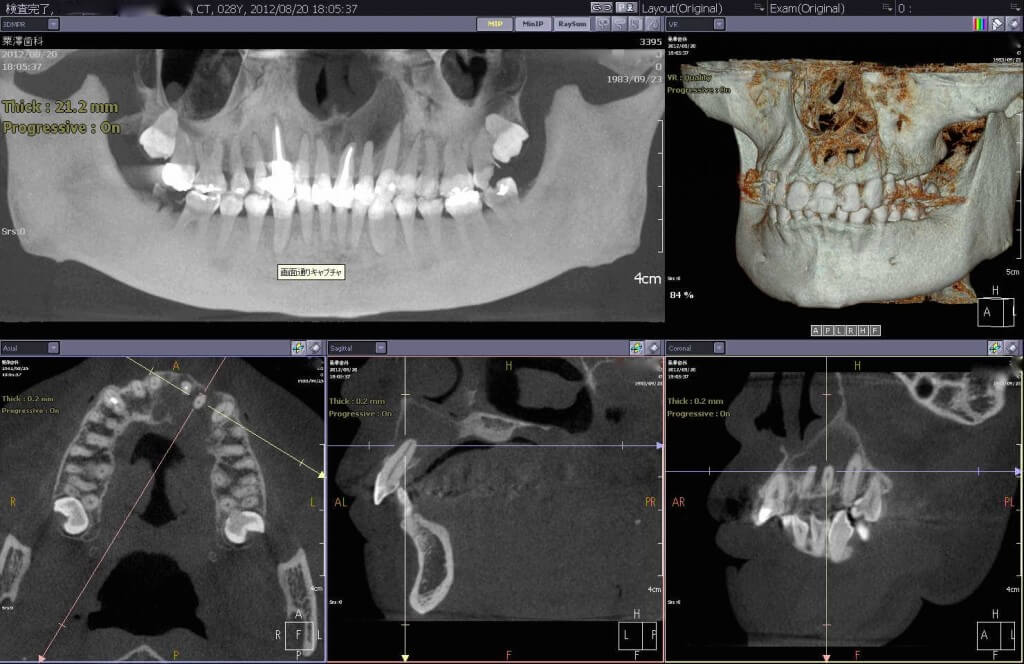

上顎前歯部に根の病気により大きな嚢胞ができてしまった症例です。CT画像で根尖部に大きな骨欠損が認められます。原因歯の歯内療法の後、嚢胞の除去並びに感染した歯根部の切除を行い、欠損部に骨補填を施しました。

病巣の処置後、ダイレクトボンディングおよびセラミッククラウンによる審美処置、保存不可能な臼歯部のインプラントによる補綴処置を行いました。